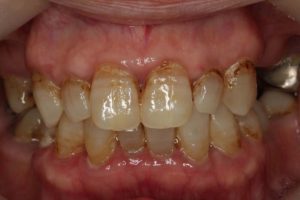

どのように変わったか、下の写真をご覧ください。

長い間お疲れ様でした。この患者さんは、奥歯を何本も失っていて満足なお食事ができない状態でした。前歯も所々虫歯で黒ずんでいて気になって口を開けて笑えないとおっしゃっていました。そもそも、最初はお嬢様の結婚の前までに綺麗にしたいというものだったのですが、治療をしていくうちに奥歯の大切さを実感していただいたようです。

奥歯にインプラントを入れ、前歯はホワイトニングやダイレクトボンディング、セラミックなどで修復しました。